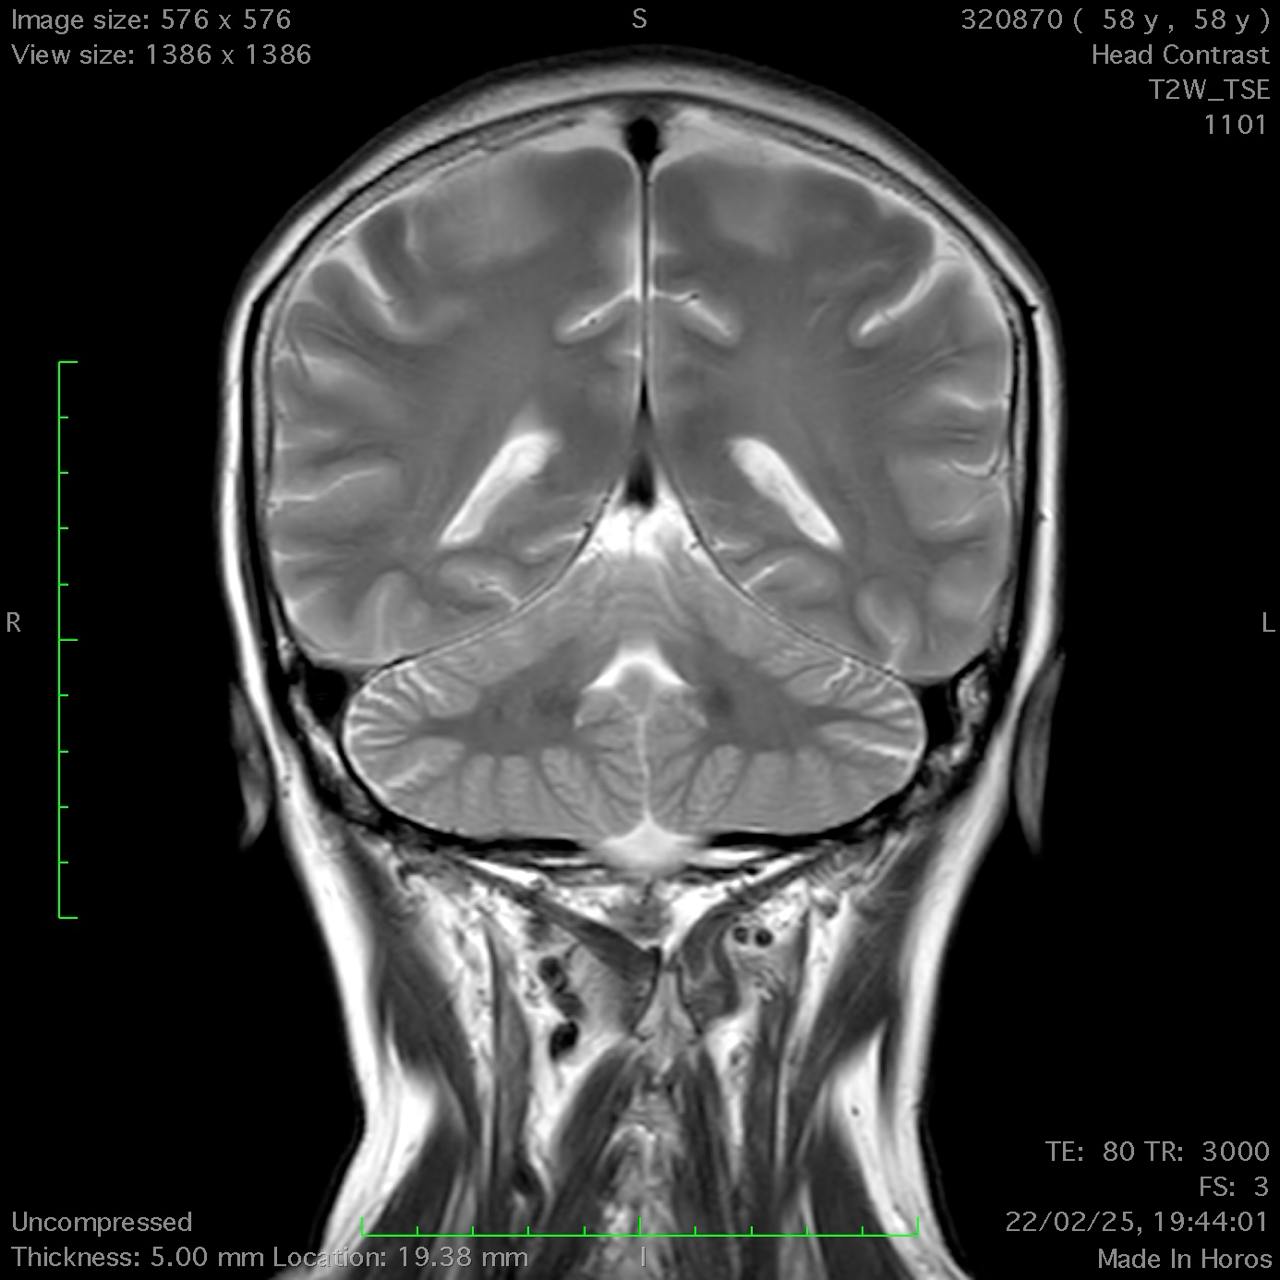

Results: Cerebellar ataxia, bilateral lower limb sensory loss, absent deep tendon reflexes, and marked bidirectional nystagmus were all found during the neurological test. Bilateral vestibular areflexia was established by video head impulse testing (vHIT). Electroneurography demonstrated sensory neuronopathy, and brain MRI showed mild cerebellar atrophy, particularly in the vermis, without evidence of central demyelination or structural abnormalities suggestive of other neurodegenerative conditions. The diagnosis of CANVAS was highly supported by the combination of clinical, electrophysiological, and imaging evidence, even if genetic confirmation was not feasible due to financial constraints CANVAS.

Conclusion: Suspicion of CANVAS should be raised in the presence of bilateral vestibular impairment, sensory neuropathy, progressive ataxia, and severe bidirectional nystagmus. The diagnosis is further supported by moderate cerebellar atrophy seen on MRI. When genetic testing is not available, a diagnosis can nevertheless be made using clinical and paraclinical findings, even though genetic testing is the gold standard for confirmation. Patient care can be enhanced, and needless treatments can be avoided, by recognizing CANVAS.

Coronal T2-weighted MRI.